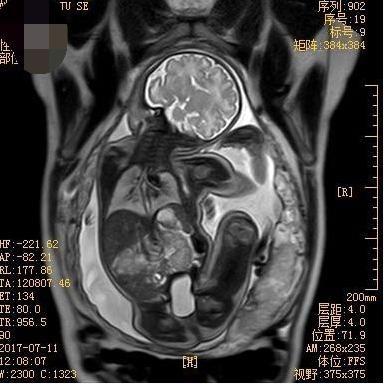

胎儿MRI视野大、软组织分辨率高、不受母体情况如肥胖、子宫肌瘤、羊水过少和多胎等影响,可清晰显示胎儿各个器官信号特点,获得超声不能显示的额外信息,常作为产前超声检查的重要补充手段。近年来,胎儿MRI诊断技术逐渐在临床得到应用并获得重视。胎儿MRI初期主要应用于胎儿神经系统的研究,近年来已经逐渐扩展到胎儿胸部、腹部、盆腔及胎盘等,研究观念从对胎儿单一脏器或系统成像发展为视胎儿为一个整体,这对诊断胎儿多发畸形有重要意义。接下来,我将给大家详细介绍关于胎儿MRI检查的适应症和禁忌症。

中枢神经系统畸形是胎儿MRI最佳适应症,特别是颅后窝畸形,胼胝体发育不良,复杂脑和脊柱畸形,脑室增大原因探查,脑和脊柱肿瘤,脑皮质发育情况评价,神经元移行异常,脑实质缺血或出血,脑、脊髓膨出内容物的鉴别等。